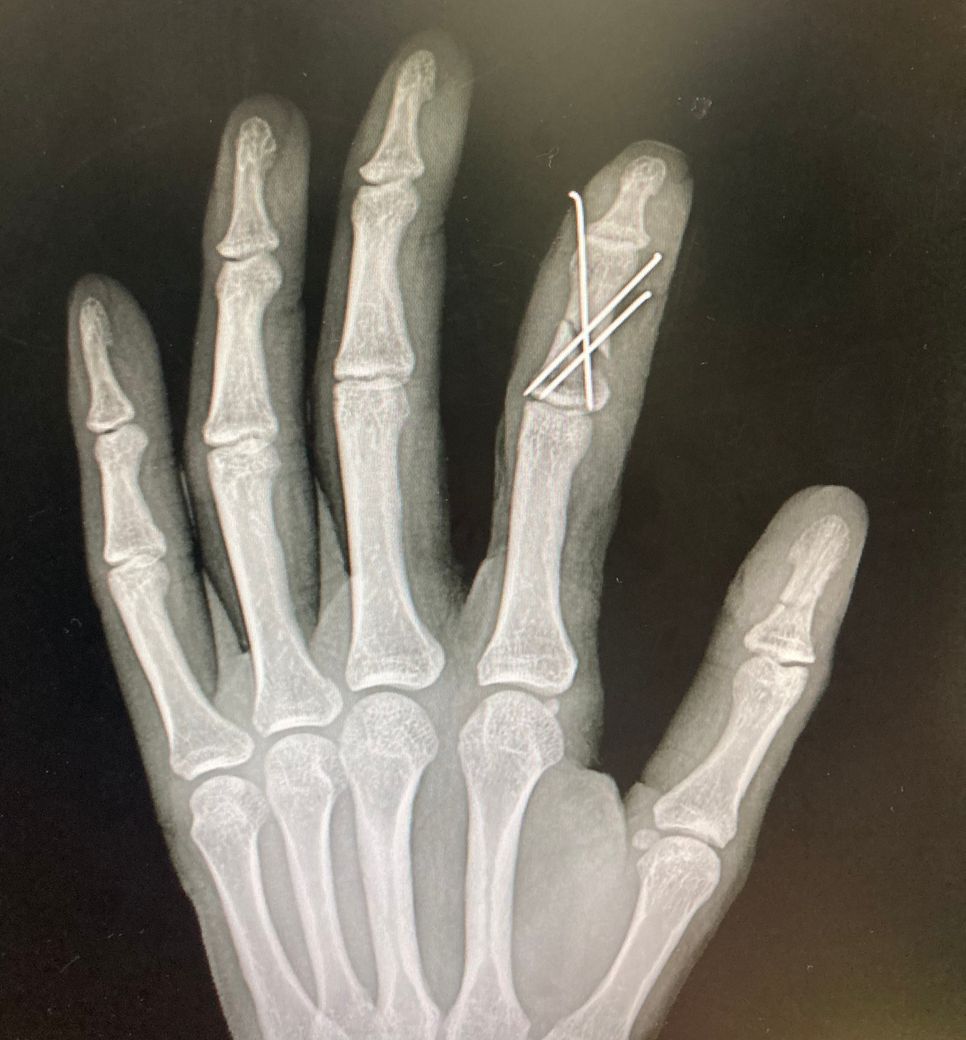

6-7주차 사진입니다 골절 부위가 좀 멀어보이

는데 유합되고있는지 될수있는지

문의드립니다

• 1번 째 사진

수지골 분쇄골절로 k-wire를 하셨네요

아직까지 엑스레이 사진에는 유합소견은 보이지 않는 것 같습니다

개인차이가 있으니 너무 불안해하지 않으셔도 됩니다

벌어져 있는 부분에 골진이 나오면서 점차 차오르고 붙을 겁니다. 지금 상태에서는 회복될 때까지 기다리는 것이 좋을 것 같습니다.